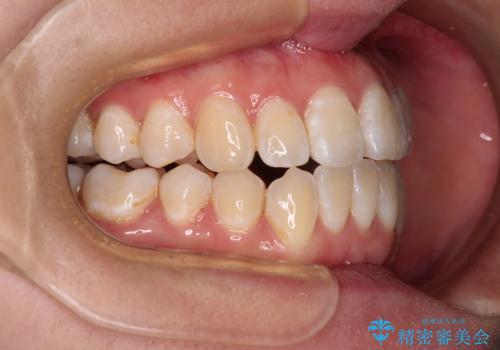

- 上下前歯の隙間と、外側を向いていて歯磨きのしにくい奥歯を気にして来院された患者様です。

下顎前歯が1本欠損しており、上下アーチはアンバランスとなりますが、インビザラインを用いて上下の隙間を改善しながら歯列を整えることとしました。

外側を向いている奥歯は、内側にアンカースクリューを埋入して牽引の固定ゲント氏、部分的にワイヤー装置を用いることで歯列に納めることとしました。